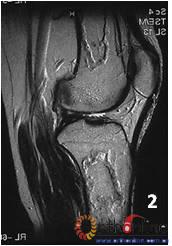

1.    单纯骨髓坏死。发生在长骨骨干及干骺端的坏死只累及骨髓组织,骨皮质很少受累,称为骨梗死(bone infarction)。坏死仅累及骨髓,不会累及皮质。(图2

2 男,40岁,激素相关骨梗死,MRI显示坏死仅累及骨髓,皮质存留:(1)股骨干和胫骨干冠状位图像;(2)股骨干和胫骨干矢状位图像;(3)股骨干横断面;(4)胫腓骨横断面

Fig 2  Male, 40 year-old, steroid-associated the bone infarction, MRI showed necrosis involved only in bone marrow, the cortical bone was preserved: (1) the coronal image of diaphysis of femur and tibia;(2) the saggital image of femur and tibia; (3) Transverse section of femur; (4) Transverse section of tibia